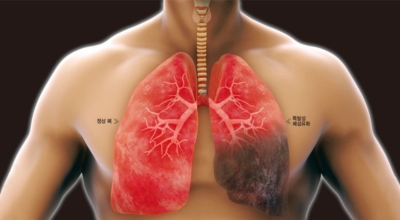

- 흡연: 흡연은 폐 기능을 저하시키고 면역력을 떨어뜨려 폐렴 발병 위험을 높입니다.

- 금연: 흡연은 폐 기능을 악화시키므로 반드시 금연해야 합니다.